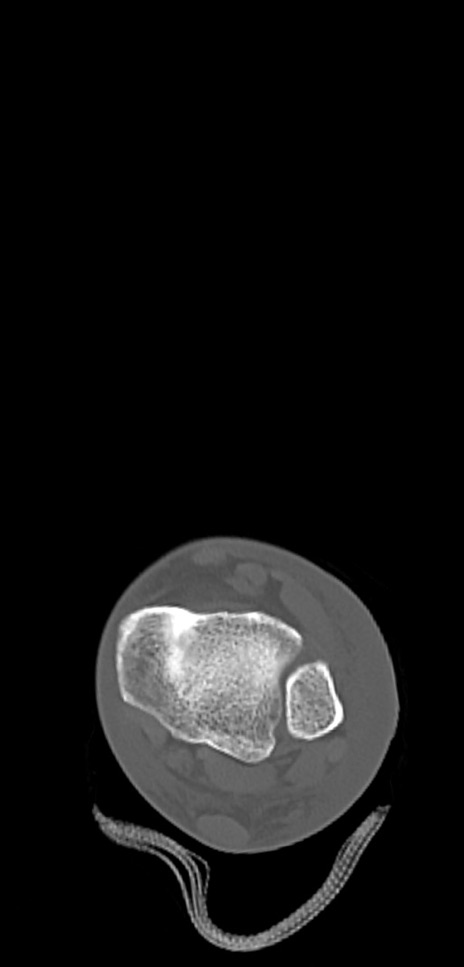

症例37 左足関節CT(横断像)

左足関節CT